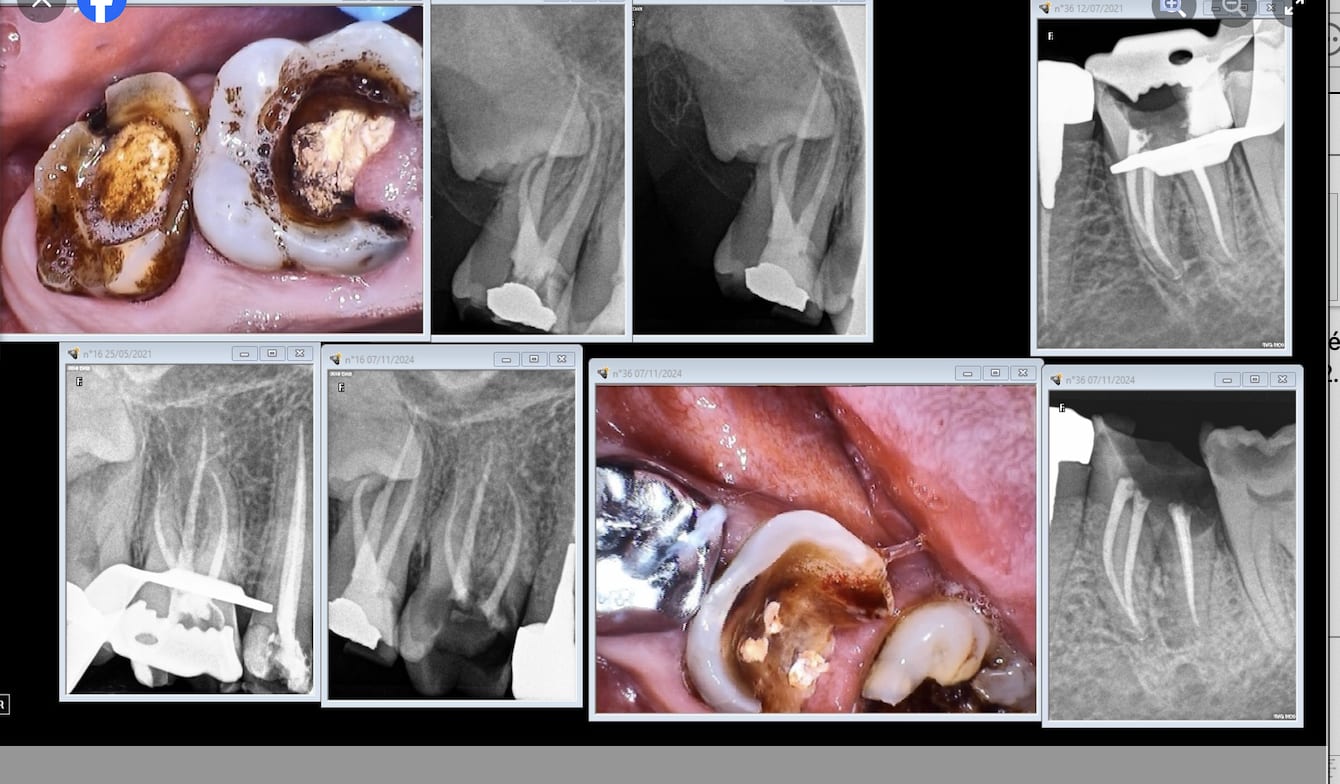

850 avec dépose de la couronne et de l’ic claveté ;)

Mais d’abord un cbct pour tenter d’évaluer les chances de guérison.

Il se dit qu’il y aurait 20 % d’échecs sur les retraitements avec foyer infectieux quand tout est mené dans les règles de l’art.

Il semble y en avoir 2 sur cette 36…